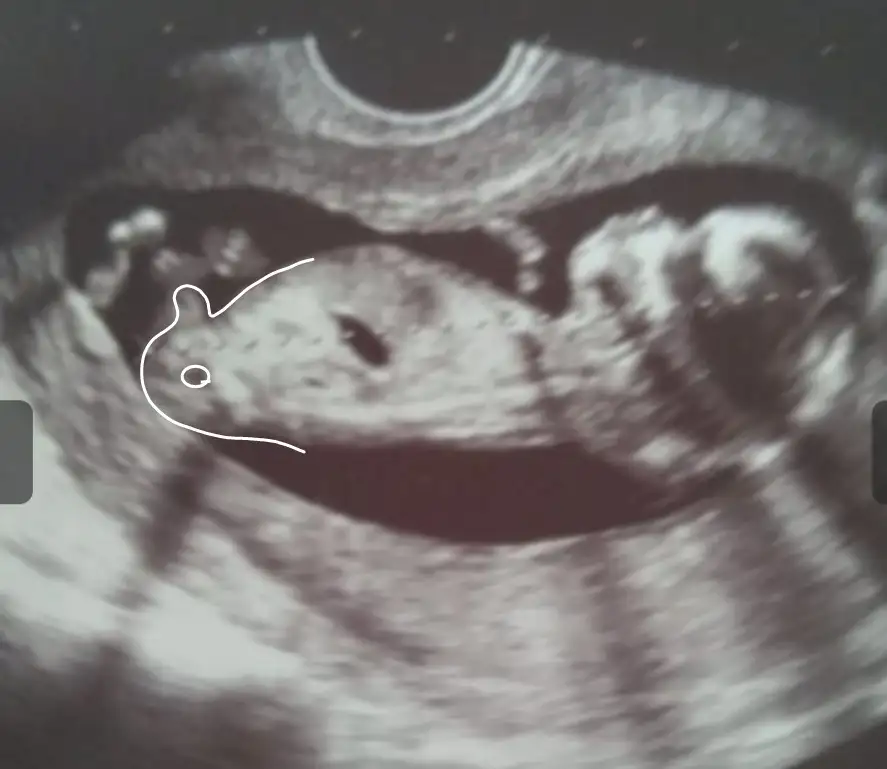

İkra meyra cnm bakabilirmisin 11haftalık